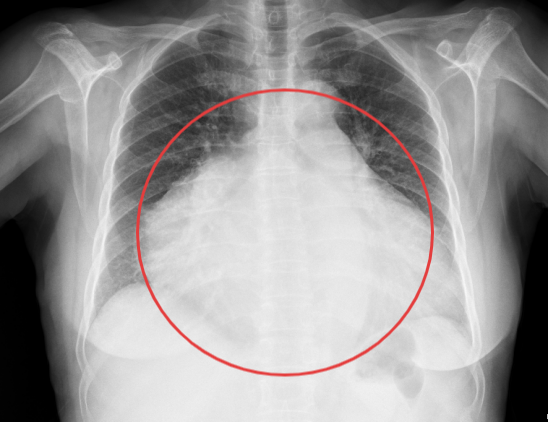

患者杨阿姨,因右下腹胀痛持续一月入院,经过详细的腹部CT检查,结果显示其腹腔内存在一个巨大占位性病变,最大层面大小竟达到了惊人的18cm×10cm×14cm,肿瘤性质及来源尚不明确。面对如此庞大的肿瘤,手术难度可想而知。然而,杨阿姨的身体状况更为复杂。术前检查发现,她全心扩大,心脏彩超显示三尖瓣大量反流,肺动脉高压、二尖瓣大量反流,肺动脉瓣中量反流,并伴有心动过缓。这些心脏问题无疑为手术增添了巨大的风险。面对这样心功能极差的患者,任何微小的失误都可能导致不可挽回的后果。